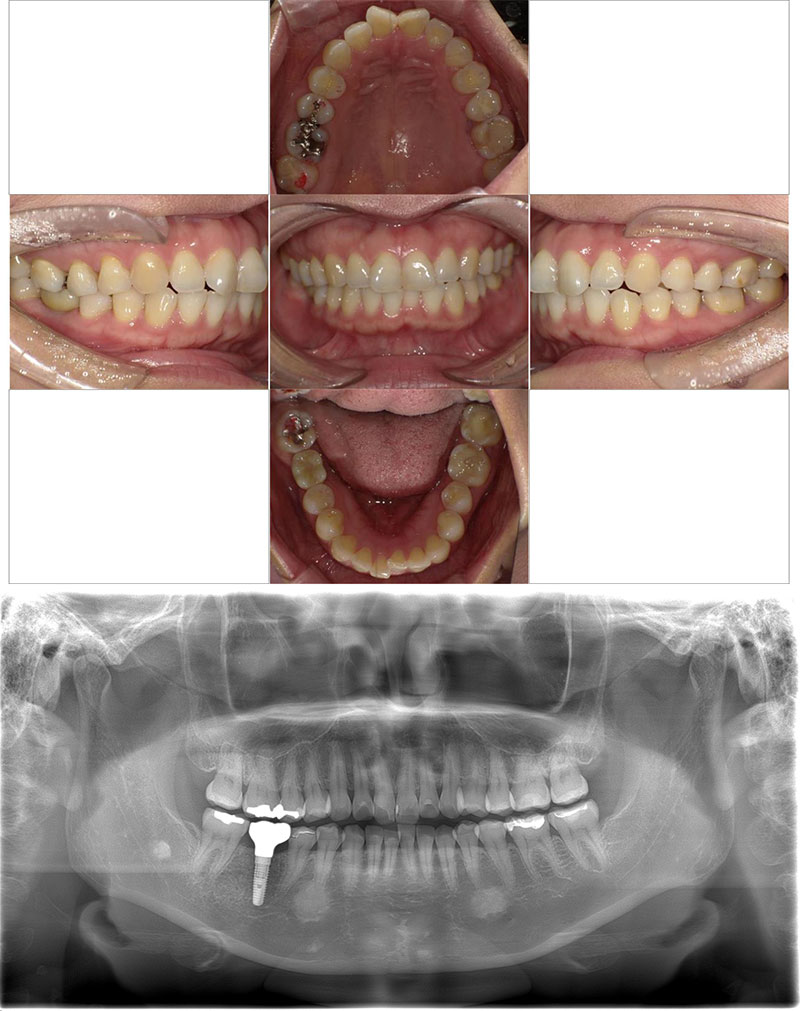

インプラント+矯正+メタルフリー症例

治療前

Before

治療後

After

年齢 38

性別 男性

主訴 全体的に歯を綺麗にしたい